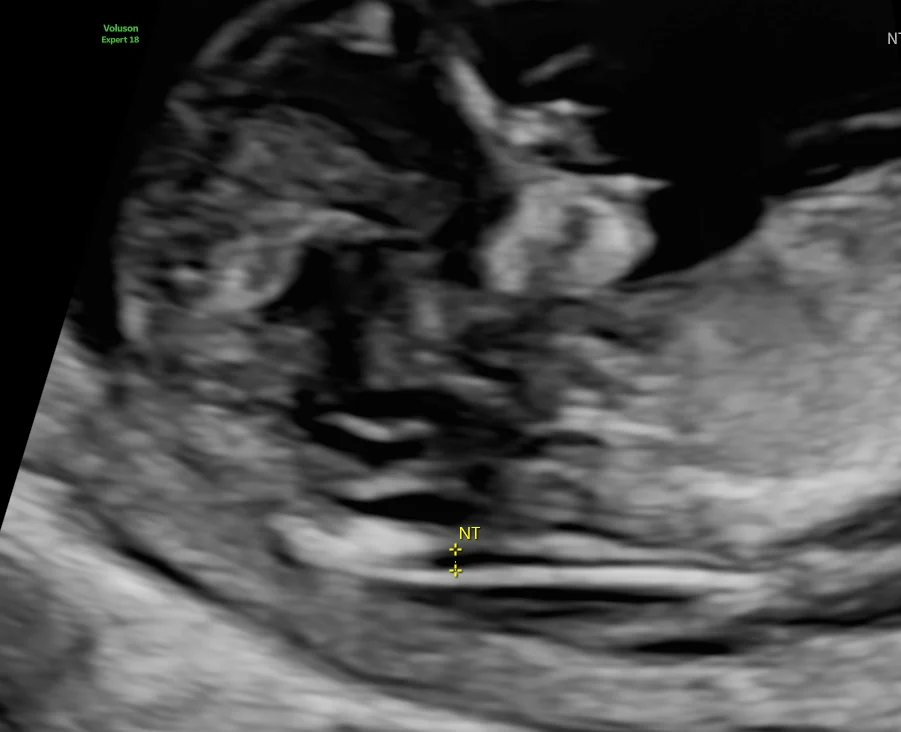

NT–NB Scan (11–14 weeks)

Early markers for chromosomal and structural abnormalities:

• Nuchal translucency

• Nasal bone

• Ductus venosus & tricuspid flow (if indicated)